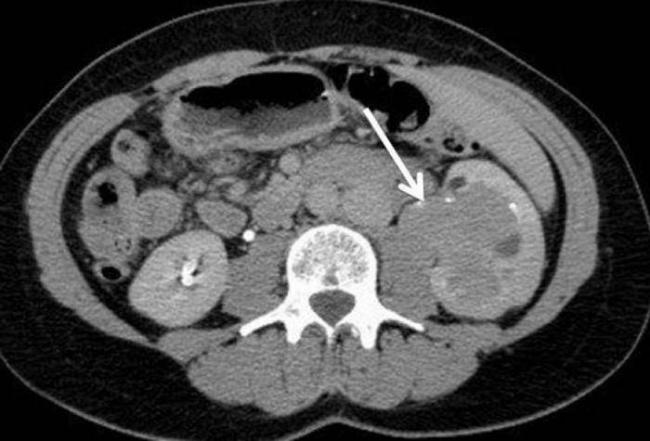

Основным методом раннего диагностирования новообразований почек является УЗИ, может применяться компьютерная магнитно- резонансная томография, рентгенологические обследования, нефросцинтиграфия ( радиоизотопное исследование).

Важная роль в организации диагностики патологии отводится ультразвуковому обследованию почек и компьютерной томографии. Часто для диагностики используется и нефросцинтиграфия.

Обзорная рентгенография или экскреторная урография не представляют никакой диагностической ценности с точки зрения организации раннего диагностирования опухолевого новообразования в почке.

С изучения состояния магистральных сосудов органа, а именно аорты, сосудов, нижней полой вены, используется МРТ с введение контрастного вещества.

Присутствие в почке опухолевого тромба помогает определить кавография, артериография, аортография при расположении новообразования в нижней полой вене. Также данные методы дают возможность выявить тип васкуляризации новообразования и наличие добавочных сосудов. Эта диагностика помогает правильно установить объем и тактику реализации хирургического вмешательства. Пункционная биопсия для почки считается дополнительным методом диагностики.

Метастазы злокачественного образования обычно проникают в кости или легкие, поэтому каждому больному при возникновении подозрений на наличие опухоли в почке проводится рентгенография, компьютерная томография черепа, легких и позвоночника.